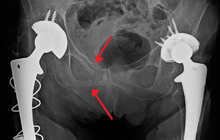

Fractures of the superior (in two places) and inferior pubic rami on the person's right, in a person who has had prior hip replacements

Pelvic fractures are most commonly described using one of two classification systems. The different forces on the pelvis result in different fractures. Sometimes they are determined based on stability or instability.[2]